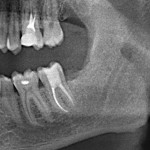

Это мой самый любимый и тщательно подготовленный проект — семинар по немедленной имплантации. Он уже дважды был в Москве, и однажды — в Нижнем Новгороде. На этот раз, мы проводим его совместно с компанией APEX в Санкт-Петербурге, и посвящен он будет… догадайтесь с трех раз?))) Через фокус немедленной имплантации будут рассмотрены различные имплантационные системы, операции остеопластики, синуслифтинга, удаления зубов и превентивной аугментации лунок.